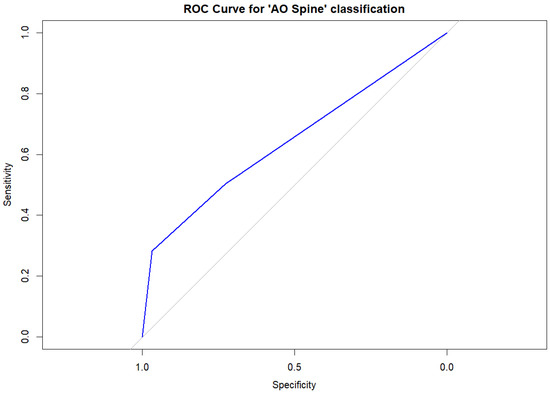

The ROC curve analysis of the AO Spine classification to predict vertebral collapse showed an area under the curve (AUC) of 0.646 (95%CI, 0.567–0.725), mainly explained by the effect of the A4 fracture type (AUC, 0.625, 95%CI, 0.574–0.676). For this category, the sensitivity and specificity for vertebral collapse were 0.282 and 0.967, respectively. Figure 3 shows the ROC curve for the AO Spine classification.

Figure 3.

Receiver operating characteristic (ROC) curve analysis for the AO Spine classification in our sample. The blue line represents the ROC curve based on the logistic regression results, where the AO Spine classification was the only significant predictive variable. The gray diagonal line corresponds to the reference of a random classification (line of no discrimination).

Third, we found that, among the different classification systems explored, only the one proposed by the AO Spine was associated with vertebral collapse. In particular, approximately two thirds of A1 fractures did not collapse. Conversely, 24 out of 28 A4 fractures collapsed in our series, while A3 fractures were very similar in both groups (collapse, 30.8%; non-collapse, 32.4%). The odds ratio for vertebral collapse in A4 vertebral fractures (using A1 as the reference standard) was 15.4, although the confidence interval was ample due to the relatively limited data available for multinomial variables in our sample. The AUC of the model for AO Spine fractures was moderate (0.646) and particularly influenced by the A4 category, with poor sensitivity (28.2%) and high specificity (96.7%), indicating that the model helps predict those fractures which will not collapse. Notably, this model only takes into account the predictive power of the AO Spine classification, which could be significantly increased with multivariate models that should be explored in future studies [3].